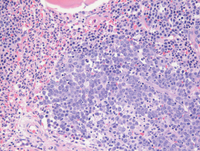

Bone core biopsy-higher power examination

On closer examination, the large sheet-like clusters of mononuclear cells are immature early erythroid precursors (proerythroblasts) forming tight clusters while the adjacent interstitial areas demonstrate prominent granulocytic proliferation including several eosinophils. Megakaryocytes are unremarkable (not shown).